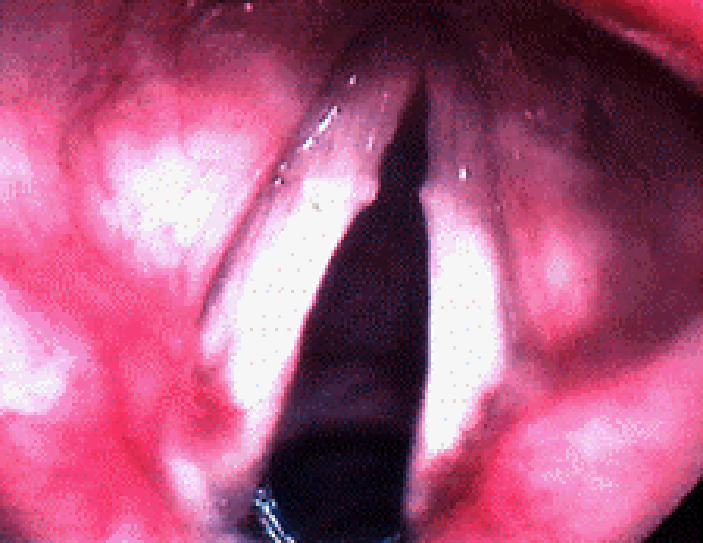

Links zie je twee typische stembandknobbels. Ze zijn gelegen op het voorste 1/3 van de stembanden. Merk op dat ze aanwezig zijn op beide stembanden en dat ze symmetrisch liggen.

- Stembandknobbels komen voor op het voorste 1/3 en het achterste 2/3 van de stembanden, omdat dat de plaats is waar de stembanden het meest contact maken tijdens het spreken.

- Ze kunnen uni- of bilateraal aanwezig zijn.